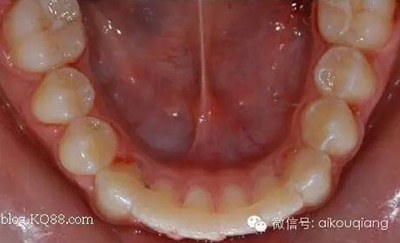

發(fā)幾張漂亮有個性的哈氏活動保持器: